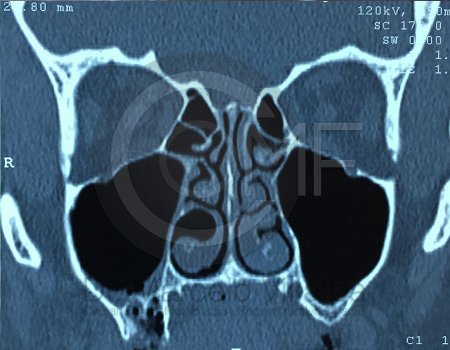

Comunicación en Seno Maxilar

Comunicacion Seno Maxilar 14